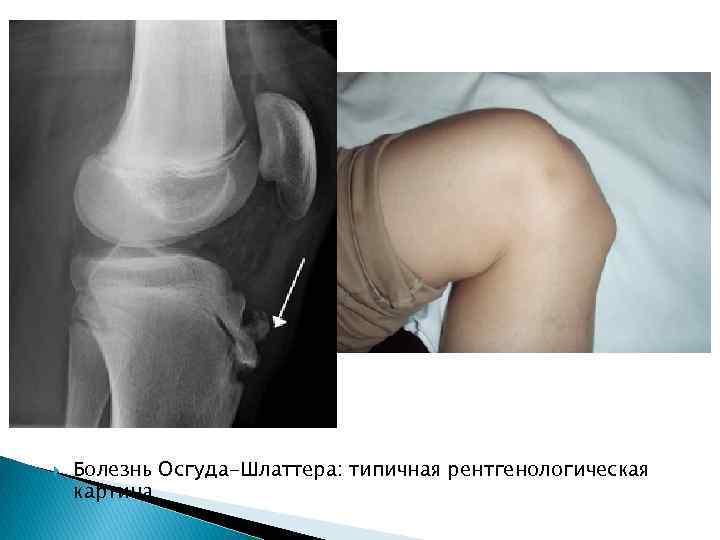

Болезнь Осгуда-Шлаттера: типичная рентгенологическая картина

Остеохондропатия бугристости большеберцовой кости (болезнь Осгуд-Шлаттера) Бугристость большеберцовой кости - образование эпифизарного происхождения. В возрасте 13 -15 лет ядро окостенения продвигается в область хрящевого tuberos. tibia в виде хоботка. На боковой рентгенограмме этот хоботообразный вырост проксимального эпифиза большеберцовой кости отделен сзади от метафиза хрящевой прослойкой. В некоторых случаях ядра окостенения может отделяться хрящевой прослойкой от костного эпифиза. Или могут наблюдаться 3 -4 ядра окостенения изолированно расположенных впереди метафиза, а хоботообразный отросток очень короткий. В 18 -19 лет происходит слияние ядер окостенения с массивом большеберцовой кости.

Остеохондропатия бугра большеберцовой кости (болезнь Осгуд-Шлаттера). Поражение бугристости большеберцовой кости носит обычно односторонний характер. Возникает и клинически проявляет себя, как правило, после травмы. Среди больных очень часто встречаются крепкие молодые люди, которые активно занимаются спортом (футболисты, легкоатлетыбегуны). Клиническая картина. В области бугристости большеберцовой кости появляются спонтанные боли, которые усиливаются при надавливании на бугристость и при сгибании коленного сустава. Определяются припухлость, небольшая отечность мягких тканей, при пальпации – твердый костный нарост. Рентгенологически определяются фрагментация или отделение бугристости от кости. Лечение заключается в ограничении ходьбы, бега, занятий физкультурой. Назначаются физиотерапевтические процедуры: теплые местные ванны, массаж, эластическая повязка на коленный сустав. Заболевание заканчивается через 1– 1, 5 года полным выздоровлением, если проводились физиотерапевтическое лечение и бальнеологические процедуры.

Рентгенологическая картина остеохондропатии бугристости большеберцовой кости очень разнообразна. Структура хобото-образного отростка представлена чередующимися участками хрящевой и некротической ткани. Может наступать полная фрагментация всей бугристости, контуры изъедены как спереди, так и со стороны метафиза. Хрящ в передних отделах бугристости утолщен, создает выпячивание мягких тканей, легко прощупывается. Утолщена хрящевая прослойка между бугристостью и метафизом, так что нижний конец хоботообразного отростка может приподниматься кпереди. В течении процесса некротические участки рассасываются, происходит перестройка костной структуры и бугристость принимает нормальный костный рисунок. Четко не удается выделить сменяющие друга фазы процесса. Остеохондропатия Осгуд - Шлаттера почти всегда заканчивается в рентгенологическом изображении полным восстановлением костной структуры. Рентгенологическое исследование имеет ограниченные возможности и без учета клинических данных диагноз может быть ошибочным, т. к. некоторые варианты окостенения имитируют патологические изменения. Не всегда помогает сравнение с аналогичным участком здоровой конечности, т. к. картина окостенения с обеих сторон может быть различной. Следует отметить, что некоторые авторы (Д. Г. Рохлин, Н. С. Дьяченко) относят болезнь Осгуд - Шлаттера к процессам травматического характера, а не к остеохондропатиям.